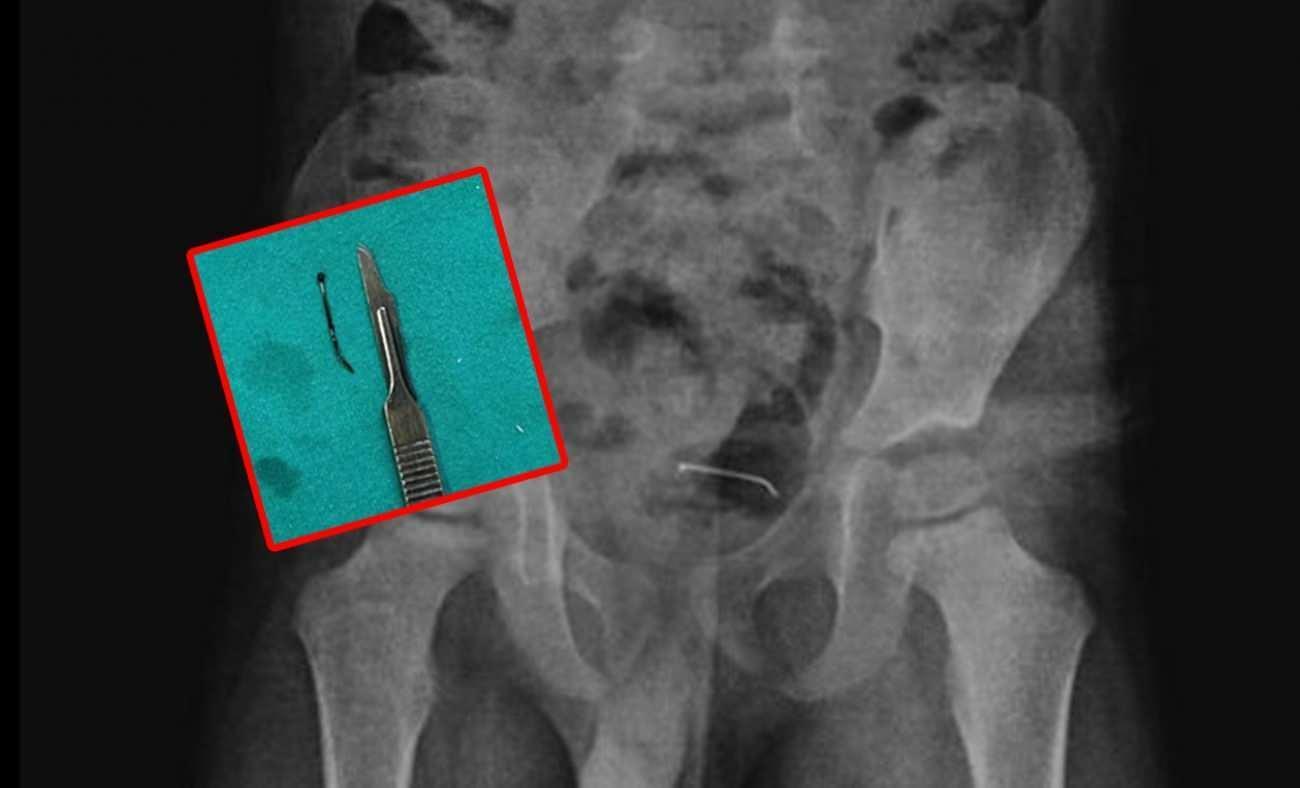

Bitlis’te, 5 yaşındaki bir çocuk oyun oynarken toplu iğne yuttu. 9 ay sonra şiddetli ağrılar yaşayan çocuk hastaneye götürüldü. Yapılan tetkikler sonucu yeri tespit edilen toplu iğne başarılı bir operasyonla alındı.

Bitlis’te oyun oynarken toplu iğne yutan 5 yaşındaki çocuk “yabancı unsur yutma” münasebeti ile ailesi tarafından hastaneye götürüldü. Hekimlerin incelemelerine karşın sonuç alamayan aile konuta geri döndü. 9 ay sonra şiddetli karın ağrısı yaşayan çocuk tekrar hastaneye götürüldü. Yapılan tetkikler sonucunda çocuğun mesane duvarında görülen ve toplu iğne olduğu tespit edilen yabancı husus başarılı bir cerrahi operasyonla alındı.

5 yaşındaki çocuğa yapılan tetkikler sonucunda, şiddetli karın ağrısına neden olan durumun mesane duvarına yapışan yabancı husus olduğu tespit edildi. Küçük çocuğun yuttuğu 3 santimetre uzunluğundaki toplu iğne başarılı bir operasyonla alındı.

3 SANTİMETRLİK TOPLU İĞNE BAŞARILI BİÇİMDE ÇIKARILDI

Kamçı, yabancı cismin bedenden olağan yollarla atılamadığını belirterek, “Bunun üzerine ameliyat kararı aldık. Ameliyatta cismin mesane duvarına yapıştığını gördük. Cerrahi operasyonla 3 santimetre civarındaki toplu iğneyi çıkardık. Hastayı birkaç gün takipte tuttuk. Genel sıhhat durumu düzgün olan hastamızı taburcu ettik.” ifadelerini kullandı.